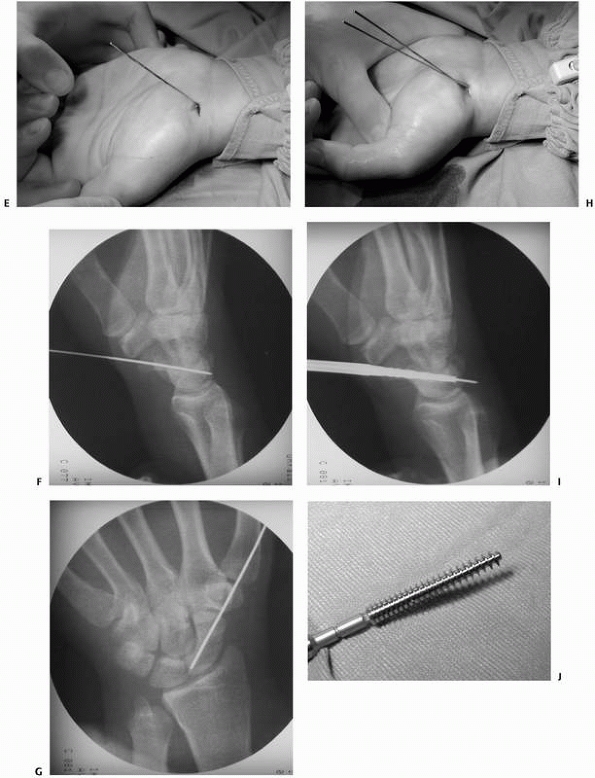

![]() |

|

FIGURE 29-19 Percutaneous stabilization of scaphoid fracture. A. AP view of scaphoid fracture in an athlete. B. The wrist should be dorsiflexed prior to insertion of the K-wire. C.

A 4 to 5 mm incision is sufficient for insertion of the screw. The incision should be placed in skin crease to avoid visible scars. D. The joint space between scaphoid and trapezium is opened under flouroscopy. (continues) |

FIGURE 29-19 (continued) E. The K-wire is inserted in a 45-degree angle at both planes. F,G. The position of the K-wire is checked by fluoroscopy. H. A second K-wire is required in unstable scaphoid fractures to prevent rotation of the fracture fragments. I. The drill is inserted. J. A variable pitch scaphoid screw. (continues)